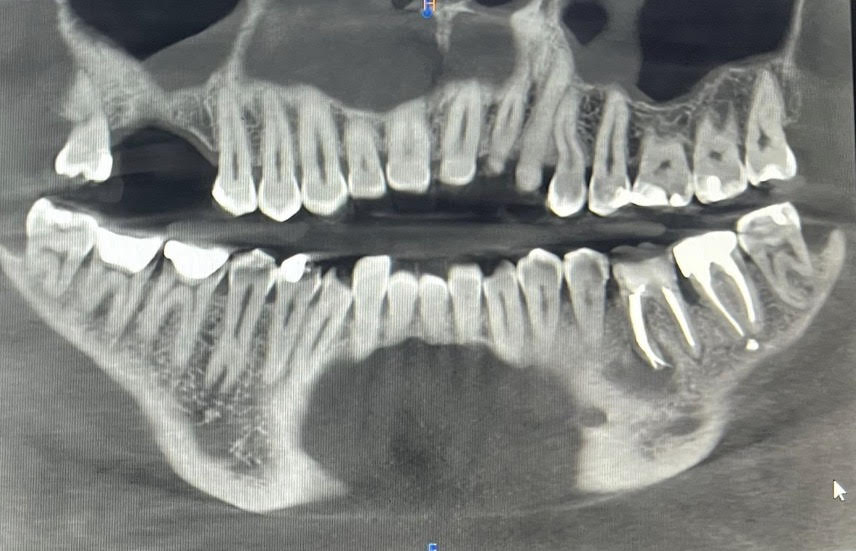

Kawitacje to obszary nieprawidłowego gojenia się kości po ekstrakcjach zębów, urazach lub stanach zapalnych. Choć często niewidoczne w standardowych badaniach radiologicznych, mogą stanowić ukryte ogniska zapalne, które oddziałują nie tylko lokalnie, ale również systemowo na cały organizm.

Dzięki zaawansowanej diagnostyce 3D i doświadczeniu zdobytemu w ramach Ghanaati Education, Joanna Śmieszek-Wilczewska potrafi analizować tomografię CBCT w taki sposób, aby rozpoznać zmiany o charakterze kawitacyjnym, a następnie określić ich potencjalny wpływ na zdrowie ogólne pacjenta.